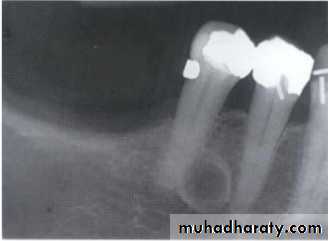

Which image is useful for R.R.T?